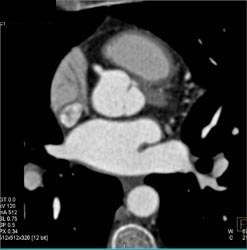

Diagnosis

Normal RCA